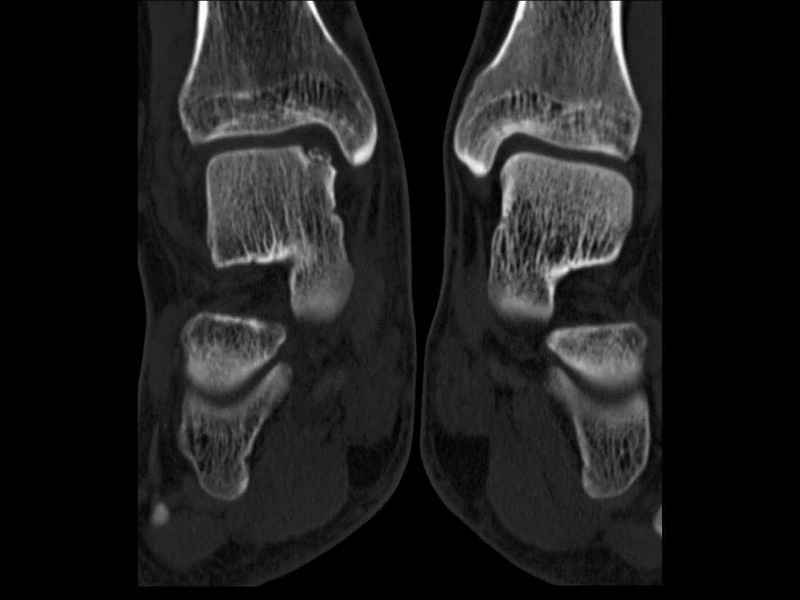

Уважаемые коллеги, обратился за помощью пациент, мужчина, 25 лет. С жалобами на болевой синдром в области голеностопного сустава и среднем отделе стопы. Травму отрицает. Со слов, болевой синдром в течении 1 года. Последние 1-1.5 мес периодически вынужден пользоваться костылями. После ограничения нагрузки боли уменьшаются.Соматически здоров. До появления болей активно занимался рукопашным боем. На СКТ картина рассекающего остеохондрита блока таранной кости, киста шейки таранной кости с признаками импрессии суставной поверхности. А также - разрастания переднего края б\берцовой кости сопровождающиеся клиникой импиджмент синдрома. Предполагаемый план лечения- удаление свободного фрагмента суставного хряща из трансмаллеолярного доступа с рассверливанием поверхности дефекта, кюретаж кисты шейки с заполнением полости биокомпозитом + дебридмент переднего отдела голеностопного сустава. Прошу высказать своё мнение, за и против, предполагаемого плана лечения. А также по возможности ответить на вопросы: 1. Есть ли необходимость в улучшении васкуляризации таранной кости (например подтаранный артродез). 2. Учитывая планируемое применение биокомпозитного цемента целесообразно ли заполнение им дефекта блока таранной кости с моделированием края суставной поверхности.